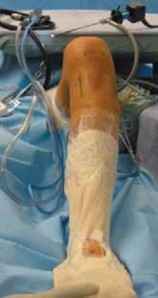

7. A padded bump is taped to the operating room table to hold the knee flexed to 90 degrees. A side post is placed on the operative side just distal to the greater trochanter to support the proximal leg with the knee in flexion (

FIG 3A

). Padded cushions are placed under the nonoperative leg.

1. After prepping and draping the operative site, a hole is cut in the stockinette for access to the dorsalis pedis pulse throughout the case (

FIG 3B

).

### FIG 3 • A. Operative field setup, demonstrating the bump holding the knee flexed to 90 degrees and a side post supporting the proximal leg with the knee in flexion. B. Stockinette with hole cut out to palpate the dorsalis pedis pulse. B #### SINGLE-BUNDLE TECHNIQUE